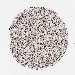

BRCA TCGA BRCA VALIDATION PROTEIN EXPRESSION